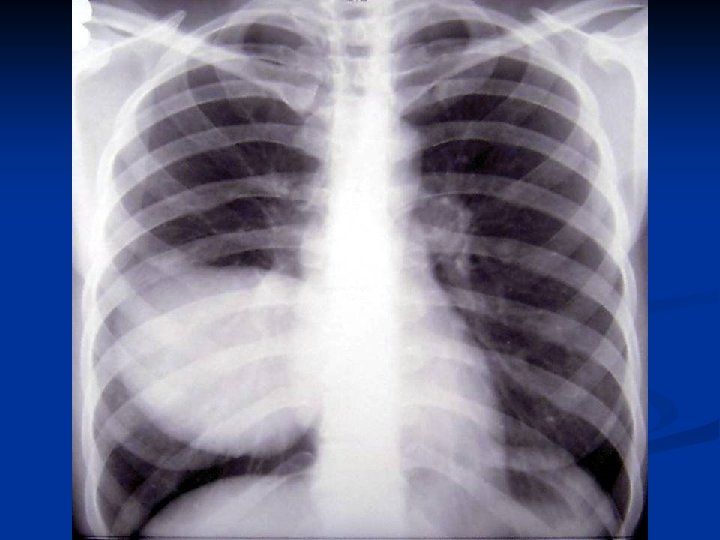

CONSIDERATII GENERALE ASUPRA CHISTULUI HIDATIC PULMONAR C. Mitrofan, A. Aldea, C. Grigorescu, I. Jitaru, C. Moldoveanu, G. Iosep, S. Bolog, M. Radulescu Clinica de Chirurgie Toracica U. M. F. Iasi

Caracteristici generale n n n Boala parazitara determinata de Taenia echinococcus granulosus. Descrisa inca de pe vremea lui Hipocrat si a lui Galen. Termenul de “chist hidatic” utilizat de Rudolphi in 1908. Localizarea pulmonara este a doua ca frecventa dupa cea hepatica. Boala cu distributie endemica in regiunea mediteraneana, Orientul Mijlociu, Australia, Noua Zeelanda, America de Sud.

Material si Metoda n Studiul de fata analizeaza retrospectiv 162 de cazuri operate in perioada 1999 – 2003.